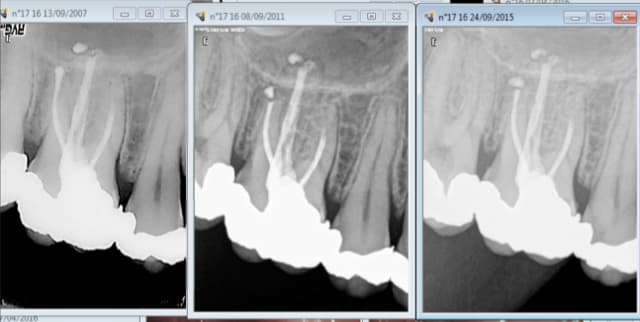

Pour bien gagner sa vie, d'après la rx initiale du premier post, faut faire une couronne sur la 6 et les compos sur 5 (et pourquoi pas 4) sont offerts au tarif conventionnel.

Le tarif conventionnel individuel de chacun des actes n'a aucun sens, mais le tarif global des 3 est acceptable.

Dans le cas présent, on peut, je pense, ne pas tomber dans ces travers: la 6 dévitalisée avec son gros amalgame mérite sa coiffe (risque de fracture, biocompatibilité des matériaux, risque de récidive carieuse sur 5 et 6 voire 7 si il y en a une, liée à l'étanchéité et à l'état de surface des reconstitutions qui ne permet pas d'éliminer la plaque de manière satisfaisante), et les amalgames sur 4 et 5 mérite aussi dans la mesure ou on refait le côté de manière moderne...et pour les mêmes raison que la 6

08/04/2016 à 13h17

JYM écrivait:

-------------

> Mais c'est du temps à expliquer tout ça! et on a pas 100 % d'acceptation!

> Donc on fait un beau compo, qui va pas durer, sauf si la 6 pète...

Je ne vois pas pour quoi il ne va pas durer si la 6 pète. -))

Par contre j'attends depuis longtemps qu'elle pète la 6. -)

Au passage pas vu en septembre dernier la reprise en distal sur la 5. Ca n'est pas du sous traitement volontaire mais involontaire. -)

Ceci dit la carie étant profonde j'ai prévenu le patient d'éventuels problèmes de sensibilité, que j'attends également pour faire un bon IC coiffe tout bien remboursé. -)